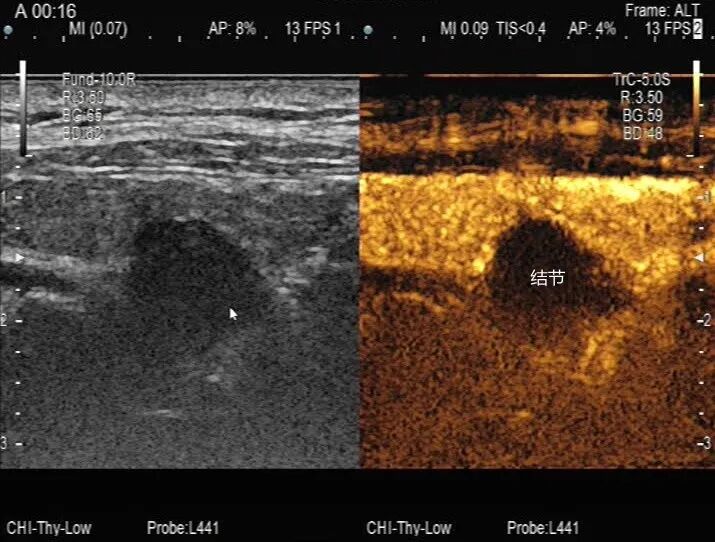

造影表現(xiàn):甲狀腺右葉低回聲結(jié)節(jié)雙期無增強(qiáng)。

超聲造影診斷:甲狀腺右葉低結(jié)節(jié) TI-RADS 2類(考慮:木乃伊結(jié)節(jié)可能性大),妥妥的良性結(jié)節(jié)。(以上是詞句是針對上幅圖的描述)